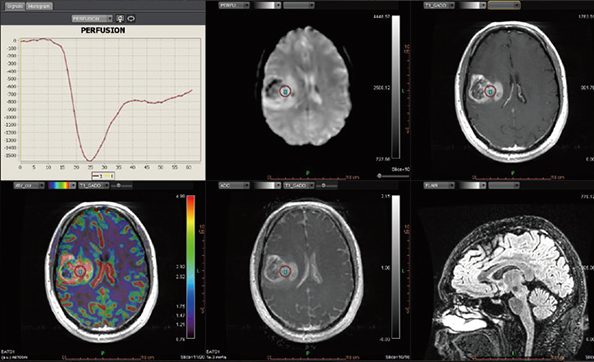

Додаток Brain Tumor Streamlined.

Додаток Brain Tumor пропонує автоматизовану покрокову обробку, включаючи кількісний мультипараметричний аналіз. Ця програма також включає оптимізований алгоритм корекції витоку контрастної речовини для підвищення точності оцінки DSC MР-перфузії.

Додаток MR Neuro

Додаток Neuro інтегрований у розширену візуалізацію Vitrea і забезпечує спеціальні протоколи для пухлини мозку та розширені протоколи інсульту, які забезпечують швидку оцінку захворювань головного мозку.

Обчислює оптимізовані параметричні карти (rBV, rBF, TTP, MTT, TMAX, tMIP) із первинної перфузійної серії

Використовує автоматизований та настроюваний робочий процес

Включає повністю автоматизовану поетапну обробку для пацієнтів з пухлинами мозку, включаючи кількісний та якісний мультипараметричний аналіз

Забезпечує корекцію витоку контрасту та створення карти K2 rBV

Пропонує один спеицифічний додаток: Розширений додаток Brain Tumor DSC DCE Expanded